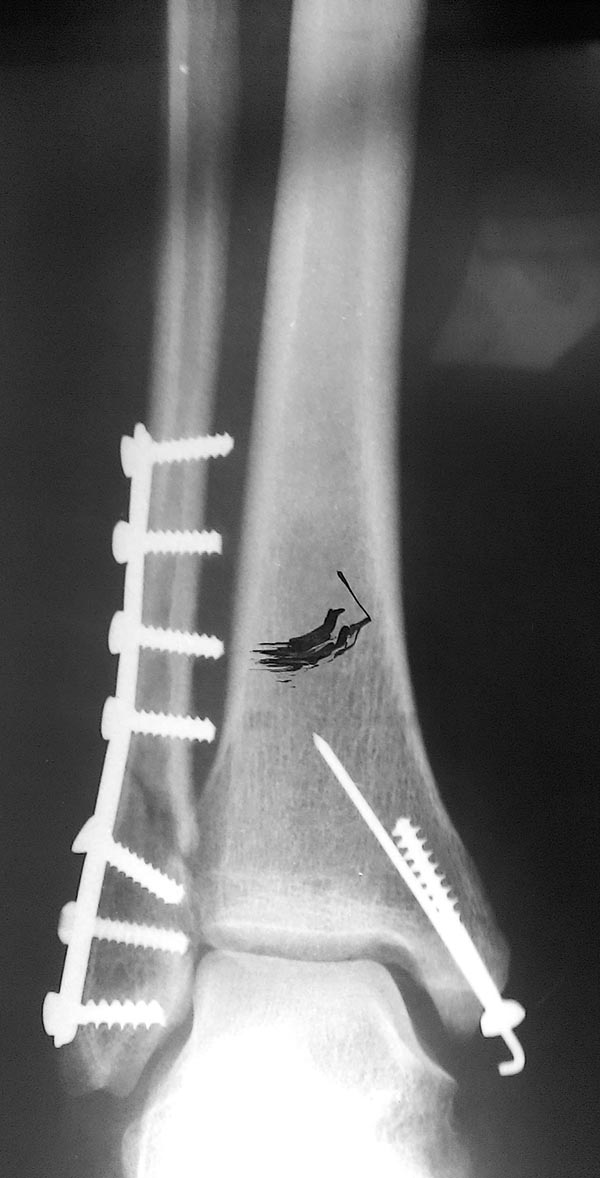

Здравствуйте. Женщина 56 лет, чрезсиндесмозный 3х-недельный перелом лодыжек.

Мнения коллег о сохраняющимся подвывихе стопы разошлись. Смущает визуальное расширение медиального лодыжечного пространства, хотя вся суставная щель примерно одинакова и равна 4-5 мм.

Для оценки желательно сделать сравнительные снимки обоих голеностопных суставов в проекции мортис, без них сложно дать ответ. Не совсем понятно полностью ли восстановлена длина латеральной лодыжки.

Подвывиха нет..Не хватает компрессионного межфрагментарного винта на наружной лодыжке, но не корично.Сделайте снимок здоровой ноги и наложите

Может быть не нужно было пластину изгибать? Как раз 1-2 мм на этом могло быть потеряно.

Пластина достаточно эластичная (1/3 трубки). Выполнить закрытую репозицию на избыточный варус под контролем ЭОП, временно фиксировать через пятку голеностопный сустав спицей ,удалить третий снизу винт, через это отверстие провести позиционный винт в большеберцовую кость, удалить фиксирующую спицу. Действительно, изгиб пластины нужно было сделать дистальнее или не делать вообще. Возможно изгиб пластины произошел самопроизвольно на свободном от винтов отверстии.